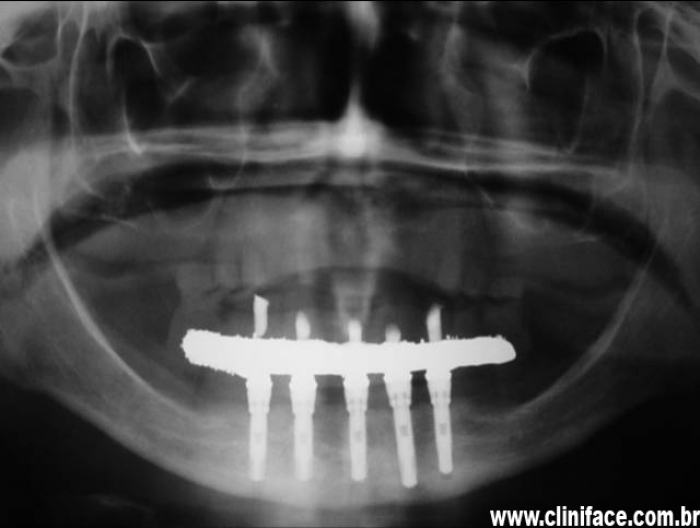

Implantes instalados

Raio X dos implantes e prótese fixa instalados